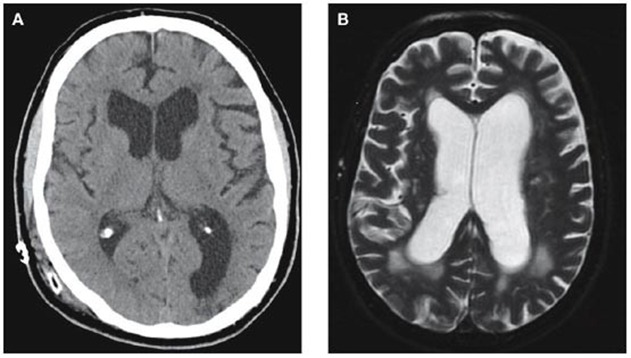

- The most important investigational imaging modalities are either a CT scan or MRI of the brain, which will show which ventricles are dilated. An enhanced CT scan or MRI will help determine the cause, as it will better define the presence of an obstructing tumor

- Ultrasound through open anterior Fontanelle is useful in assessing ventricular size in infants